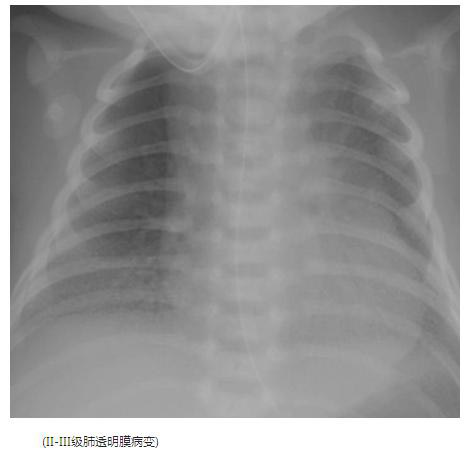

典型胸片结果: